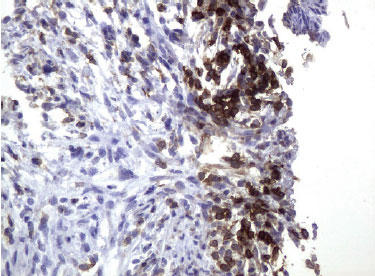

![]() 図.3 パラフィン包埋したヒト子宮内膜組織の腺がんをanti-UM500048 マウスモノクローナル抗体を使って免疫組織化学染色(UM500048) |